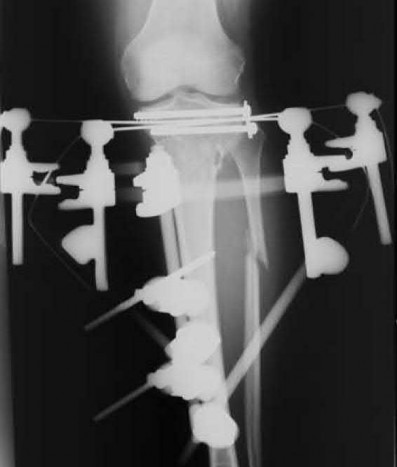

Question 20

A 3-year-old girl is evaluated for severe, progressive bilateral genu varum. Radiographs demonstrate medial metaphyseal beaking, fragmentation, and depression of the proximal medial tibial physis.

According to the Langenskiöld classification of infantile Blount's disease, at which stage does an overt physeal bony bar (epiphyseal-metaphyseal bridge) definitively form across the medial physis, conferring a high risk of recurrence without bar excision?

Explanation

The Langenskiöld classification describes progressive radiographic changes in infantile Blount disease. Stage I-IV show worsening metaphyseal beaking and stepping. Stage V shows a deep cleft separating the medial epiphysis into two portions. Stage VI is definitively characterized by the formation of a solid medial physeal bridge (bony bar) between the epiphysis and metaphysis, halting medial growth completely and often requiring bar resection along with osteotomy.